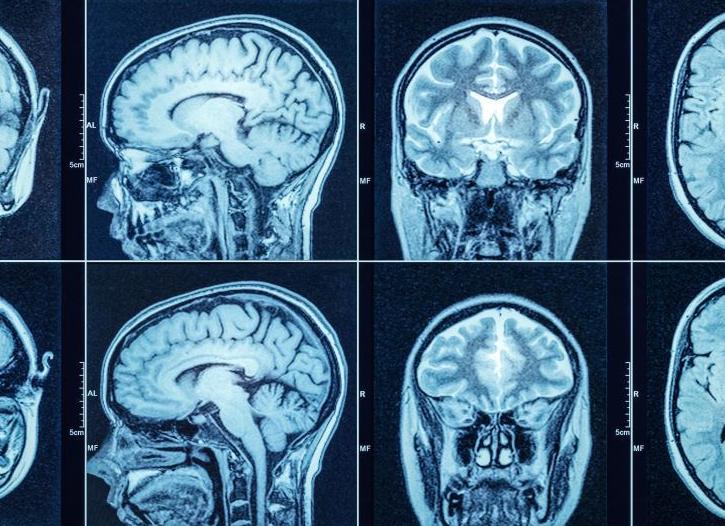

Компьютерная томография головы – незаменимая процедура для оценки состояния головного мозга.

Ситуации, при которых требуется делать томографию головы, возникают довольно часто: эта процедура незаменима, когда нужно обследовать головной мозг, сосуды головы и шеи, а также костную ткань.